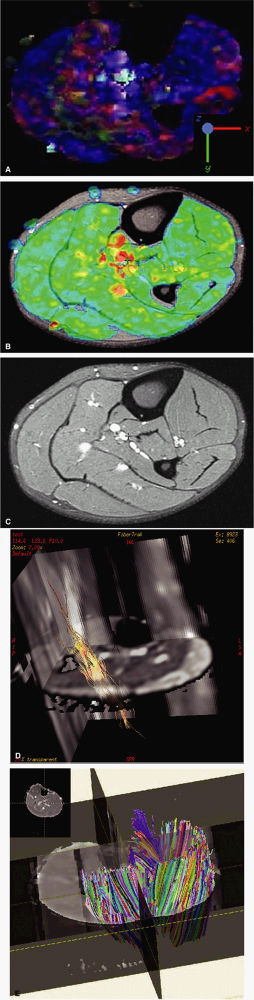

|

to as anisotropic diffusion. Fiber tracts or myelin sheaths, for example, may limit the direction in which molecules can move. Diffusion tensor imaging (DTI) is a form of DWI that images the directional information of structures such as white matter tracts (Fig. 1.24). Recent advances allow the diffusion data to be processed in color 3D to highlight the trajectories of continuous anisotropy, which are closely correlated with the physical fiber patterns. These direction-encoded color maps, DTI fiber tractography, are depictions of neuronal networks.

![]() |

FIGURE 1.24 ● Diffusion anisotropy. (A) Free water shows non-oriented diffusion behavior. (B) Posterior view of motor innervation. White matter tracts or muscle fibers show diffusion properties that reflect the orientation or path of the tracts or fibers. In the medulla oblongata corticospinal axons cross the midline in the pyramidal decussation. Ventral roots (motor) reach skeletal muscles through the peripheral nerves.

FIGURE 1.25 ● Examples of diffusion tensor MRI in calf muscle. (A) Blue indicates diffusion along the S-I axis. (B) Fractional anisotropy shows the degree of anisotropy regardless of direction. Control image (C) and fiber-tracking display using two different rendering techniques (D, E).